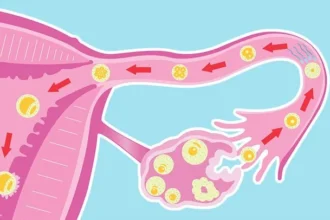

Top Gynecological Issues Every Woman Should Know About

Women’s reproductive health is a crucial aspect of overall well-being. Unfortunately, many women ignore early symptoms of gynecological issues until…

How Hormonal Changes Affect Women’s Gynecological Health

Hormones play a vital role in maintaining women’s reproductive and overall health. These chemical messengers…